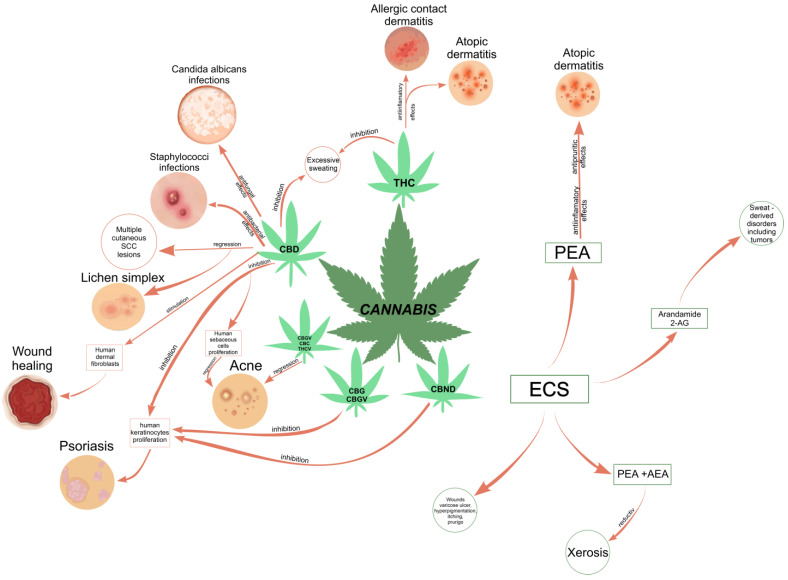

Consequently, Cannabis plant-derived compounds have been recommended for the treatment of many skin disorders and diseases, such as dry/seborrheic skin and acne [ref. 30]; atopic dermatitis (or eczema); psoriasis and resulting outcome scars [ref. 28,ref. 51]; pruritus, including neuropathic itch [ref. 52]; pain [ref. 53]; and mycosis fungoides, the most common type of cutaneous T-cell lymphoma (CTCL) [ref. 33]. An international cross-sectional survey study demonstrated that cannabinoid-based medicine (CBM) may alleviate pain and pruritus and improves wound healing and well-being in patients with epidermolysis bullosa (EB), a group of clinically and genetically heterogeneous genetic skin conditions that express fragile skin and mucosae [ref. 54]. In vivo studies demonstrated that, individually or combined, cannabinoids may reduce tumor growth or tumor cell proliferation and promote apoptosis and autophagy in melanoma cells, emerging as potential agents for the treatment of cutaneous melanoma [ref. 55]. Lichen simplex chronicus and multiple cutaneous squamous cell carcinoma (SCC) lesions have completely regressed with the topical application of 20% CBD oil [ref. 56]. Psoriasis, which emphasizes two clinical manifestations, psoriasis vulgaris and psoriatic arthritis, is the most common autoimmune skin disease that currently affects about 4% of the population [ref. 51]. pCBs are known as candidate drugs in the treatment of psoriasis due to their effects of inhibiting the proliferation of keratinocytes and modulating the associated inflammatory response [ref. 57]. Acne vulgaris (acne) affects 9.4% of the world’s population and 85% of adolescents [ref. 58]. CBD is well known for its anti-inflammatory effects on acne [ref. 58]. Both CBG and cannabigerovarin (CBGV) exert potential in the treatment of skin dryness, while CBC, cannabidivarin (CBDV), and Δ(9)-tetrahydrocannabivarin (THCV) have been proposed as novel anti-acne agents due to their efficacy [ref. 30]. In regions where cannabis use is legal, there are reported clinical cases where topical formulations including phytocannabinoids (CBD and THC), self-initiated by patients or prescribed by certain dermatologists and prepared by pharmacists, have been shown to be effective in treating a variety of skin conditions [ref. 59,ref. 60,ref. 61].

The human endocannabinoid system consists of the two cannabinoid receptors CB1 and CB2; several endogenous ligands such as 2-arachidonoylglycerol (2-AG) and N-arachidonoylethanolamine (anandamide) (AEA); and enzymes involved in the synthesis, transport, and degradation of endocannabinoids [ref. 2]. Both CB1 and CB2 skin receptors, which are present in epidermal keratinocytes, cutaneous nerve fibers, dermal cells, melanocytes, eccrine sweat glands, and hair follicles [ref. 96,ref. 97,ref. 98], can be modulated by endocannabinoids, with the most studied being N-arachidonoyl ethanolamide (AEA), 2-arachidonoyl glycerol (2-AG), N-palmitoyl ethanolamide (PEA), N-alpha-linolenoyl ethanolamide (ALEA), N-linoleoyl ethanolamide (LEA), N-oleoyl ethanolamide (OEA), N-stearoyl ethanolamide (SEA), N-eicosapentaenoyl ethanolamide (EPEA), and N-docosahexaenoyl ethanolamide (DHEA) [ref. 99,ref. 100,ref. 101,ref. 102,ref. 103]. However, endocannabinoids also bind to other receptors found in various skin cells, such as transient receptor potential (TRP) channels, which are involved in a variety of processes, including the development and preservation of the skin barrier, cell growth stimulation, and cell differentiation. They also play a significant role in immunological and inflammatory processes [ref. 72]. Endocannabinoids interact with PPARs via direct or indirect signaling pathways. Biological processes like neuroprotection, anti-inflammation, and analgesic action are partially mediated by PPAR activation [ref. 59]. ECS’s involvement and role in cutaneous biology is currently an intensely debated research topic both in clinical and preclinical studies [ref. 104,ref. 105]. Topical applications of cannabinoids provide therapeutic benefits for the patient in multiple pathologies like psoriasis, eczema, and atopic dermatitis, as shown in Figure 1 [ref. 59]. These advantages are obtained due to the remarkable role of the ECS in improving dermatological conditions symptoms such as itching, inflammation, and pain.